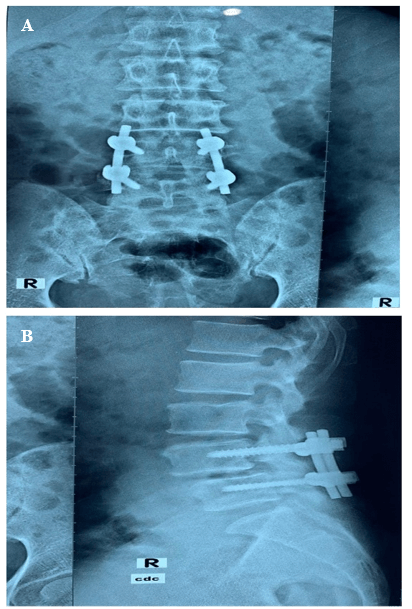

A 45-year-old female was presented with the complaints of low backache with sciatica for 4 years. The pain increased on walking and relieved by taking rest. She was nondiabetic and normotensive. On examination there was a weakness in both extensors of the toes; SLR, Deep tendon reflexes were normal. She had dysaesthesia on both L5 dermatomes. MRI of LS Spine (Figure 1) revealed a prolapsed disc at L4/5. On dynamic X-ray, LS spine revealed grade 1 spondylolisthesis (L4 over L5) (Figures 2 & 3). The patient was subjected to decompression, stabilization at L4 and L5 by pedicle screw, with L4/5 fusion. The post-operative period was uneventful, and she was well recovered. Patient follow-up was conducted periodically. She was relieved of symptoms after 2 years of follow-up, with a complete range of spine motion.

Figure 2: Functional X-ray Lumbosacral spine reveals L4/5 spondylolisthesis in Flexion view.

Figure 3: A) & B) Postoperative X-ray Lumbosacral spine showing transpedicular screw fixation with fusion at L4/5.

It this study, the patient went through decompression, adjustment using pedicle screw at L4 and L5 with the combination at L4/5. It is recommended that even decompression may prompt the destabilization of the motion segment. In later studies, it has been demonstrated that instrumented combination brings about an improved and expanded fusion rate after posterolateral fusion for degenerative spondylolisthesis, even though there are no critical contrasts in clinical results regarding pain and daily life activities [17, 18]. Our study findings are intriguing and propose that it should be considered a conceivably helpful system in patients with clinical manifestations and indications of neurogenic claudication that might be caused by spondylolisthesis, which is occult on plain radiography or traditional MRI.